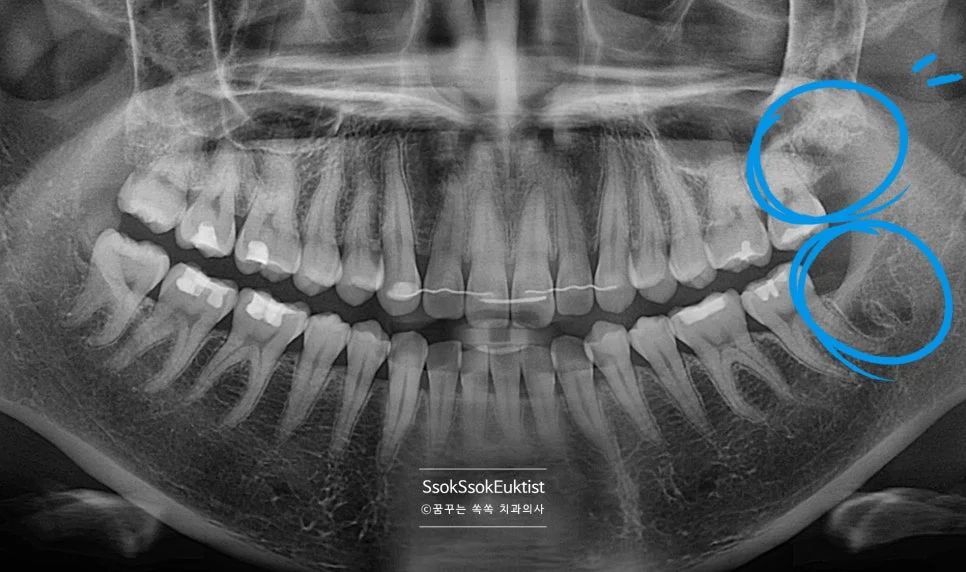

중간 난이도 완전 매복 사랑니 파노라마 엑스레이

잇몸 하방에 완전히 묻혀 있는 완전 매복 사랑니입니다. 사랑니가 맹출 하면서 잇몸의 통증을 호소하는데요, 뒤의 턱뼈와의 공간이 부족하여 어차피 매복될 치아라 바로 발치를 말씀드립니다.

깊숙이 매복되어 있어 잇몸 절개를 하고, 치아 상방의 치조골을 일부 삭제를 하고, 잘 나올 수 있게끔 사랑니 머리를 분리한 후 발치를 시행합니다.

발치 전 CT를 보면 신경관과 맞닿아 있어 발치 난도가 높은 케이스임을 알 수 있습니다.

신경관 근접 매복 사랑니 엑스레이

잔존 뿌리 없이 발치가 아주 잘 된 모습이고요^^